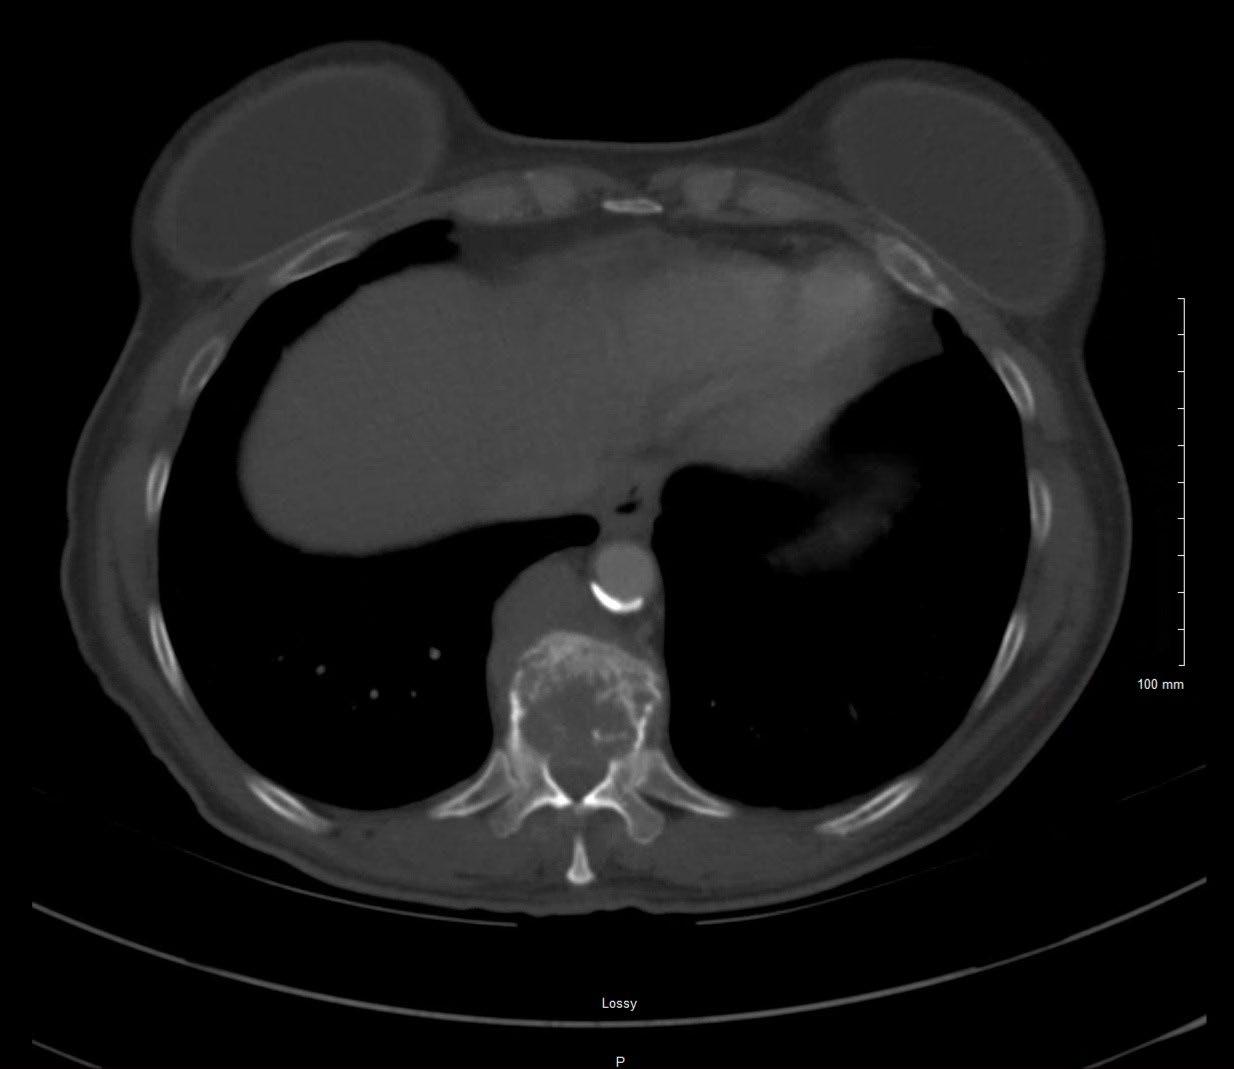

Imaging

Hillengass 2019 Lancet Oncol, Rome 2017 Clin J Oncol, Faiman 2014 Clin Lymphoma Myeloma Leuk, Dimopoulous 2009 Leukemia

Edelstyn 1967 Clin Radiol, Hillengass 2017 BCJ